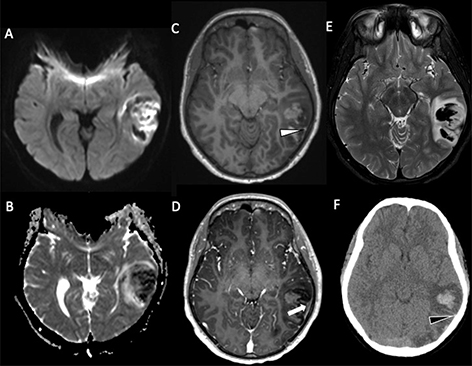

Fig 1

Figure 1. A six-month-old male who presented with acute right hemiparesis. DWI (A) demonstrates acute infarct in the left basal ganglia and deep white matter (white arrow). MRA (B) shows severe stenosis of the left M1 middle cerebral artery segment (black arrow). Follow-up 4 months later, demonstrates evolution of the infarct, now with encephalomalacia and gliosis without new acute infarct (white arrowhead) (C). MRA at that times shows mild improvement but persistent MCA stenosis (black arrowhead) (D). Findings are most compatible with focal cerebral arteriopathy.